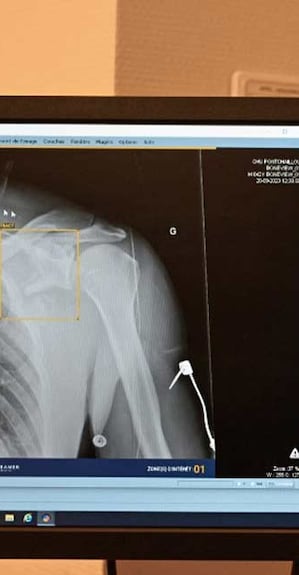

• AI is already used in diagnosis and clinical care, for instance to assist diagnosis in fields such as radiology and medical imaging, tuberculosis and oncology.

• AI-assisted X-rays could potentially detect health problems, such as tuberculosis, COVID-19, to further strengthen national diagnostic capacities.